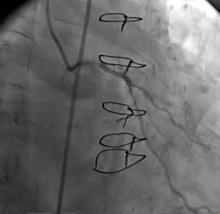

A CLs guiding catheter was used to engage the left coronary artery, and a Choicd floppy guidewire passed through the lesion. The lesion was predilated with a 1.5x15mm and 2x10mm Maveric balloon (figure 4). Then a 3.5x18mm Xience v stent was deployed at 16atm (figure 5, figure 6, figure 7). Post-dilation was done with a 4x10mm Firestar NC balloon (figure 8). The final result showed TIMI-III flow with no residual stenosis (figure 9).